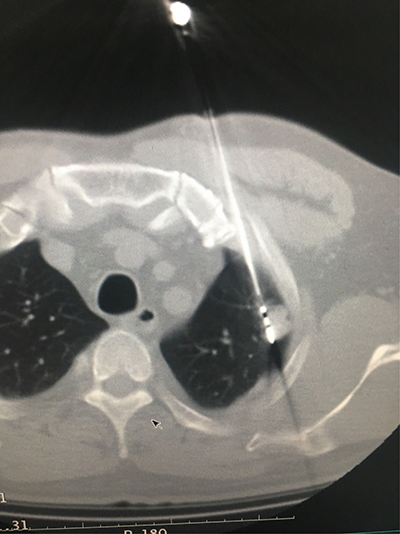

![]() | ![]() |

| (脑肿瘤的介入治疗) | (子宫肌瘤的介入治疗) |